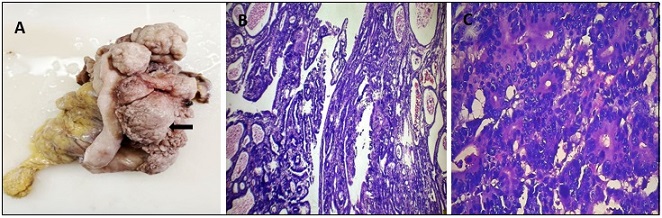

Synchronous multiple primary malignancies are rare clinical condition, and the occurrence of triple synchronous primary tumors are exceptionally uncommon. Among these, the simultaneous occurrence of primary gastric, renal, and ovarian tumor has seldom been reported in the literature. We present a case of a 70 year- female who presented with abdominal pain and endoscopic biopsy showed gastric adenocarcinoma. CECT abdomen and pelvis subsequently revealed an incidental right renal and ovarian tumor. The patient underwent curative surgical resection for all three tumors in a single operative session. Post-surgical histopathology confirmed Clear cell renal cell carcinoma and Ovarian mature cystic teratoma. There was no evidence of metastasis among the tumors. Elderly patient with gastric carcinoma have a higher risk of developing a synchronous tumor than younger people. This case highlights the importance of thorough diagnostic evaluation of multiple primary malignancies in an elderly patients with gastric cancer , as the differentiation between metastatsis and synchronous primaries significantly influences the planning of treatment. Early detection and multidisciplinary approach are essential for optimizing outcomes in such rare and complex presentations.